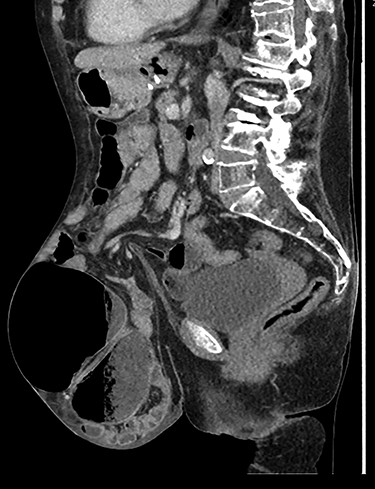

A clinical diagnosis of bowel obstruction was made; she underwent a CT abdomen/pelvis with contrast, which demonstrated a large bowel obstruction within the hernia not caused by the hernial defect but thought likely due to volvulus of the caecum (Figs. 1 and 2).

Caecal volvulus through wide-necked abdominal wall defect with small amount of free fluid in pelvis (sagittal).